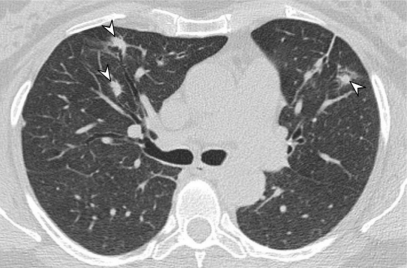

Scans